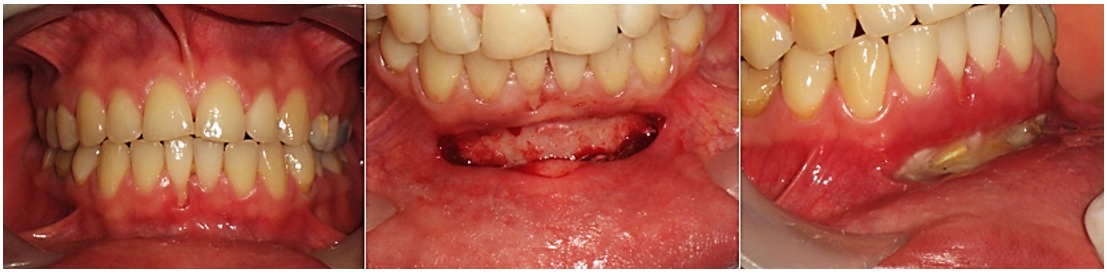

Para iniciar el procedimiento se anestesió la zona con técnica infiltrativa de Seldin con lidocaína al 2 % y epinefrina 1:80.000. Se realizó una incisión en sentido horizontal en la mucosa móvil, en el área de los incisivos laterales inferiores, siguiendo el contorno del fondo del vestíbulo, con mango de bisturí de Bard Parker n.o 3 y hoja de bisturí n.o 15 en dirección perpendicular al campo quirúrgico. Con ayuda de una pinza Adson sin garra se posicionó el tejido vestibularmente para permitir al operador visualizar la zona. Se desbridó mediante un corte agudo hasta llegar al periostio, el cual se eliminó con una espátula 7ª, para exponer hueso. Con ayuda de suturas internas, se ubicó el tejido mucoso en una posición más apical valiéndose del periostio, que estaba por debajo del campo quirúrgico. Se suturó con catgut crómico 4/0. La zona del corte horizontal se dejó sin sutura para promover una cicatrización por segunda intención. Se irrigó con solución salina al 0,9 % y se cubrió la zona con cemento quirúrgico desde el tercio medio de los incisivos inferiores hasta cubrir por completo la herida (figura 1). Al finalizar el procedimiento se prescribió terapia analgésica con nimesulida de 100 mg cada 12 h durante 3 días y antibiótica con amoxicilina de 500 mg cada 8 h durante 7 días. Se dieron además recomendaciones postoperatorias al paciente.

A los 7 días del procedimiento se evaluó la formación de tejido granular correspondiente al proceso normal de cicatrización. Después, a los 10 días se buscaba encontrar formación de tejido de cicatrización, pero aún con tejido eritematoso. A los 45 días se debía apreciar una cicatrización casi completa con formación de una banda fibrosa en el área de la incisión.

El tratamiento de defectos periodontales precisa un correcto diagnóstico en el que se determinen la gravedad de las condiciones anómalas y su etiología. De esta manera se podrán planear los mejores tratamientos posibles para frenar el avance y subsanar los defectos periodontales que se puedan presentar. En las recesiones gingivales, las superficies radiculares de los dientes están expuestas al medio bucal, lo que puede ser causado por la migración de la encía marginal y el epitelio de unión en sentido apical (7,11,12). Los casos clínicos presentados en este artículo correspondían a pacientes con recesiones grados I (sin sobrepasar la línea mucogingival, sin pérdida de tejido interdental), II (sobre o más allá de la línea mucogingival, sin pérdida de tejido interdental) y III (más allá de la línea mucogingival, con pérdida de tejido interdental pero coronal a la recesión), según Miller. Los pacientes mostraron cambios favorables después de la vestibuloplastia con técnica de Edlan Mejchar, con disminución de las recesiones de más del 60 % a los 45 días luego de los procedimientos. Los pacientes estaban satisfechos por la simplicidad de la técnica, postoperatorios sin complicaciones y resultados rápidos. Además, con la técnica se eliminaron los factores etiológicos de las afecciones. Estas características se podrían considerar como ventajas de esta técnica con respecto a otras, como el injerto de tejido conjuntivo, que se considera el estándar. Algunas de las dificultades del injerto son la necesidad de trabajar en dos campos quirúrgicos y mayores dificultades durante el periodo postoperatorio.